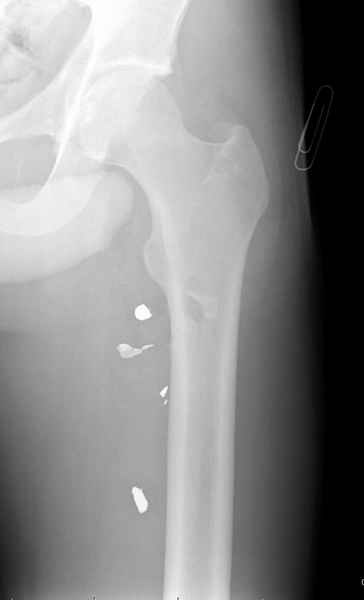

огнестрельный перелом

Больной с огнестрельным переломом бедра с вовлечением около 15% медиального кортекса, входное отверстие около 1 см в диаметре; стабильный, без сосудистых и неврологических признаков.

Что делать: гипс, костыли, операция?